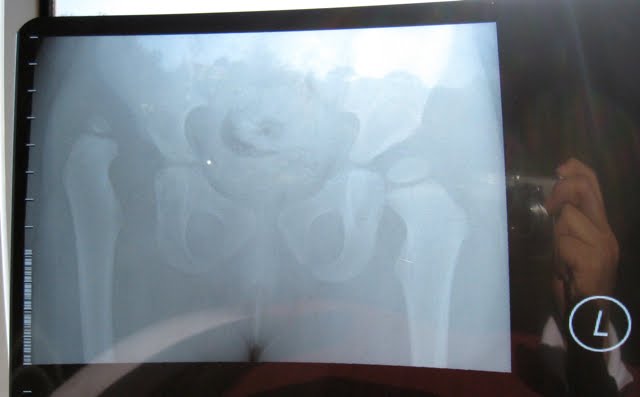

Sure enough the GP found her legs were uneven in length with the right foot being shorter, the uneven hip crease was quite evident and when Elsa walked the GP noticed the tip-toeing. We got sent off for an x-ray the following day and I could tell by looking at it that her right hip was not right. That afternoon we met with an orthopaedic surgeon who examined Elsa and confirmed she did have a dislocated right hip and would require surgery.